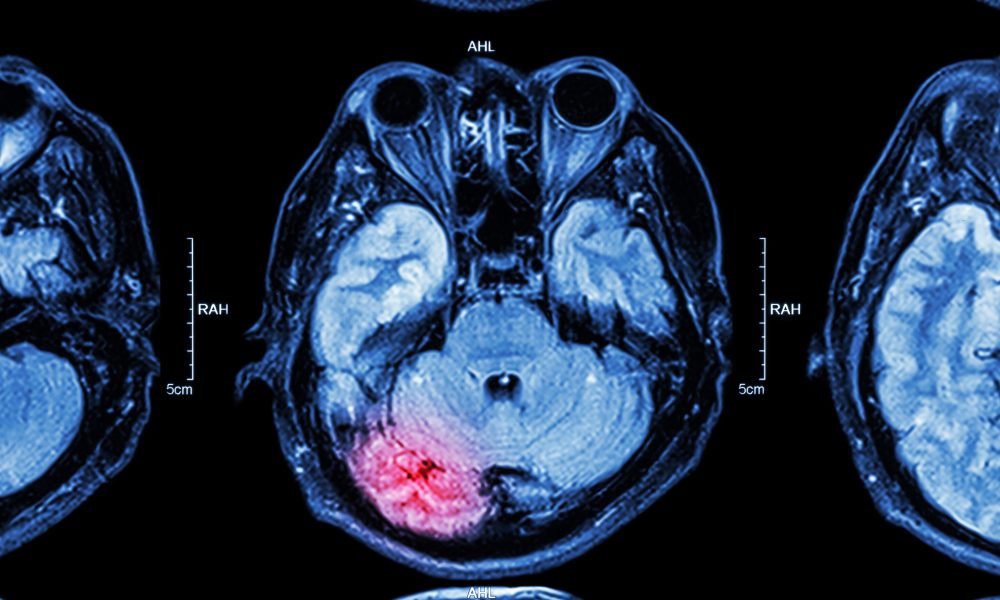

A large infarction also had to be visible on non-contrast computed tomography (NCCT) or MRI.